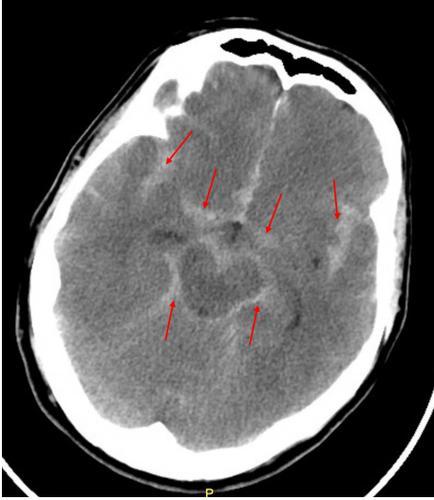

大约20%的动瘤患者在病后10至14天可能发生再出血,这会使死亡率几乎翻倍不过,急性期动静脉畸形再出血的情况相对少见另一个重要并发症是脑血管痉挛CVS,这种痉挛发生在蛛网膜下腔血液环绕的血管中其严重程度与蛛网膜下腔出血量有关,可导致超过三分之一的病例出现脑实质缺血,引发轻偏瘫等。